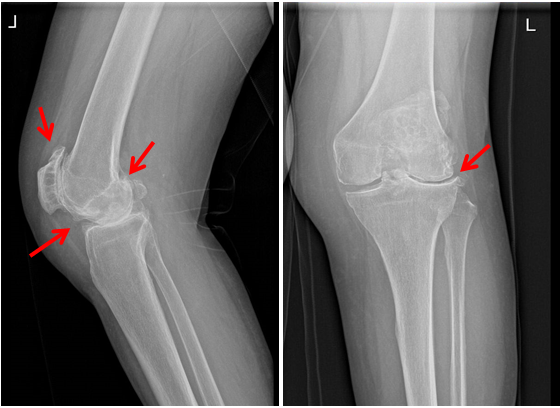

施主任在认真询问病史及阅片后告诉马女士,她两侧膝关节的软骨几乎都已经磨光了,关节表面长了许多骨刺,关节间隙非常狭窄,双下肢的外观畸形也十分明显。马女士除了走路疼痛之外,膝关节的活动度也变得很差,无法正常伸直和弯曲,确实只能选择做全膝关节置换手术。考虑到右侧膝关节的症状更重,决定先实施右侧的手术,等过半年以后再行另外一侧的手术治疗。于是在所有准备工作安排妥当之后,施主任和周志杰副主任医师一起为马女士进行了右全膝人工关节置换术,整个手术过程非常顺利。

术前的X片提示:双侧的膝关节重度退变,骨刺增生明显,关节间隙狭窄。